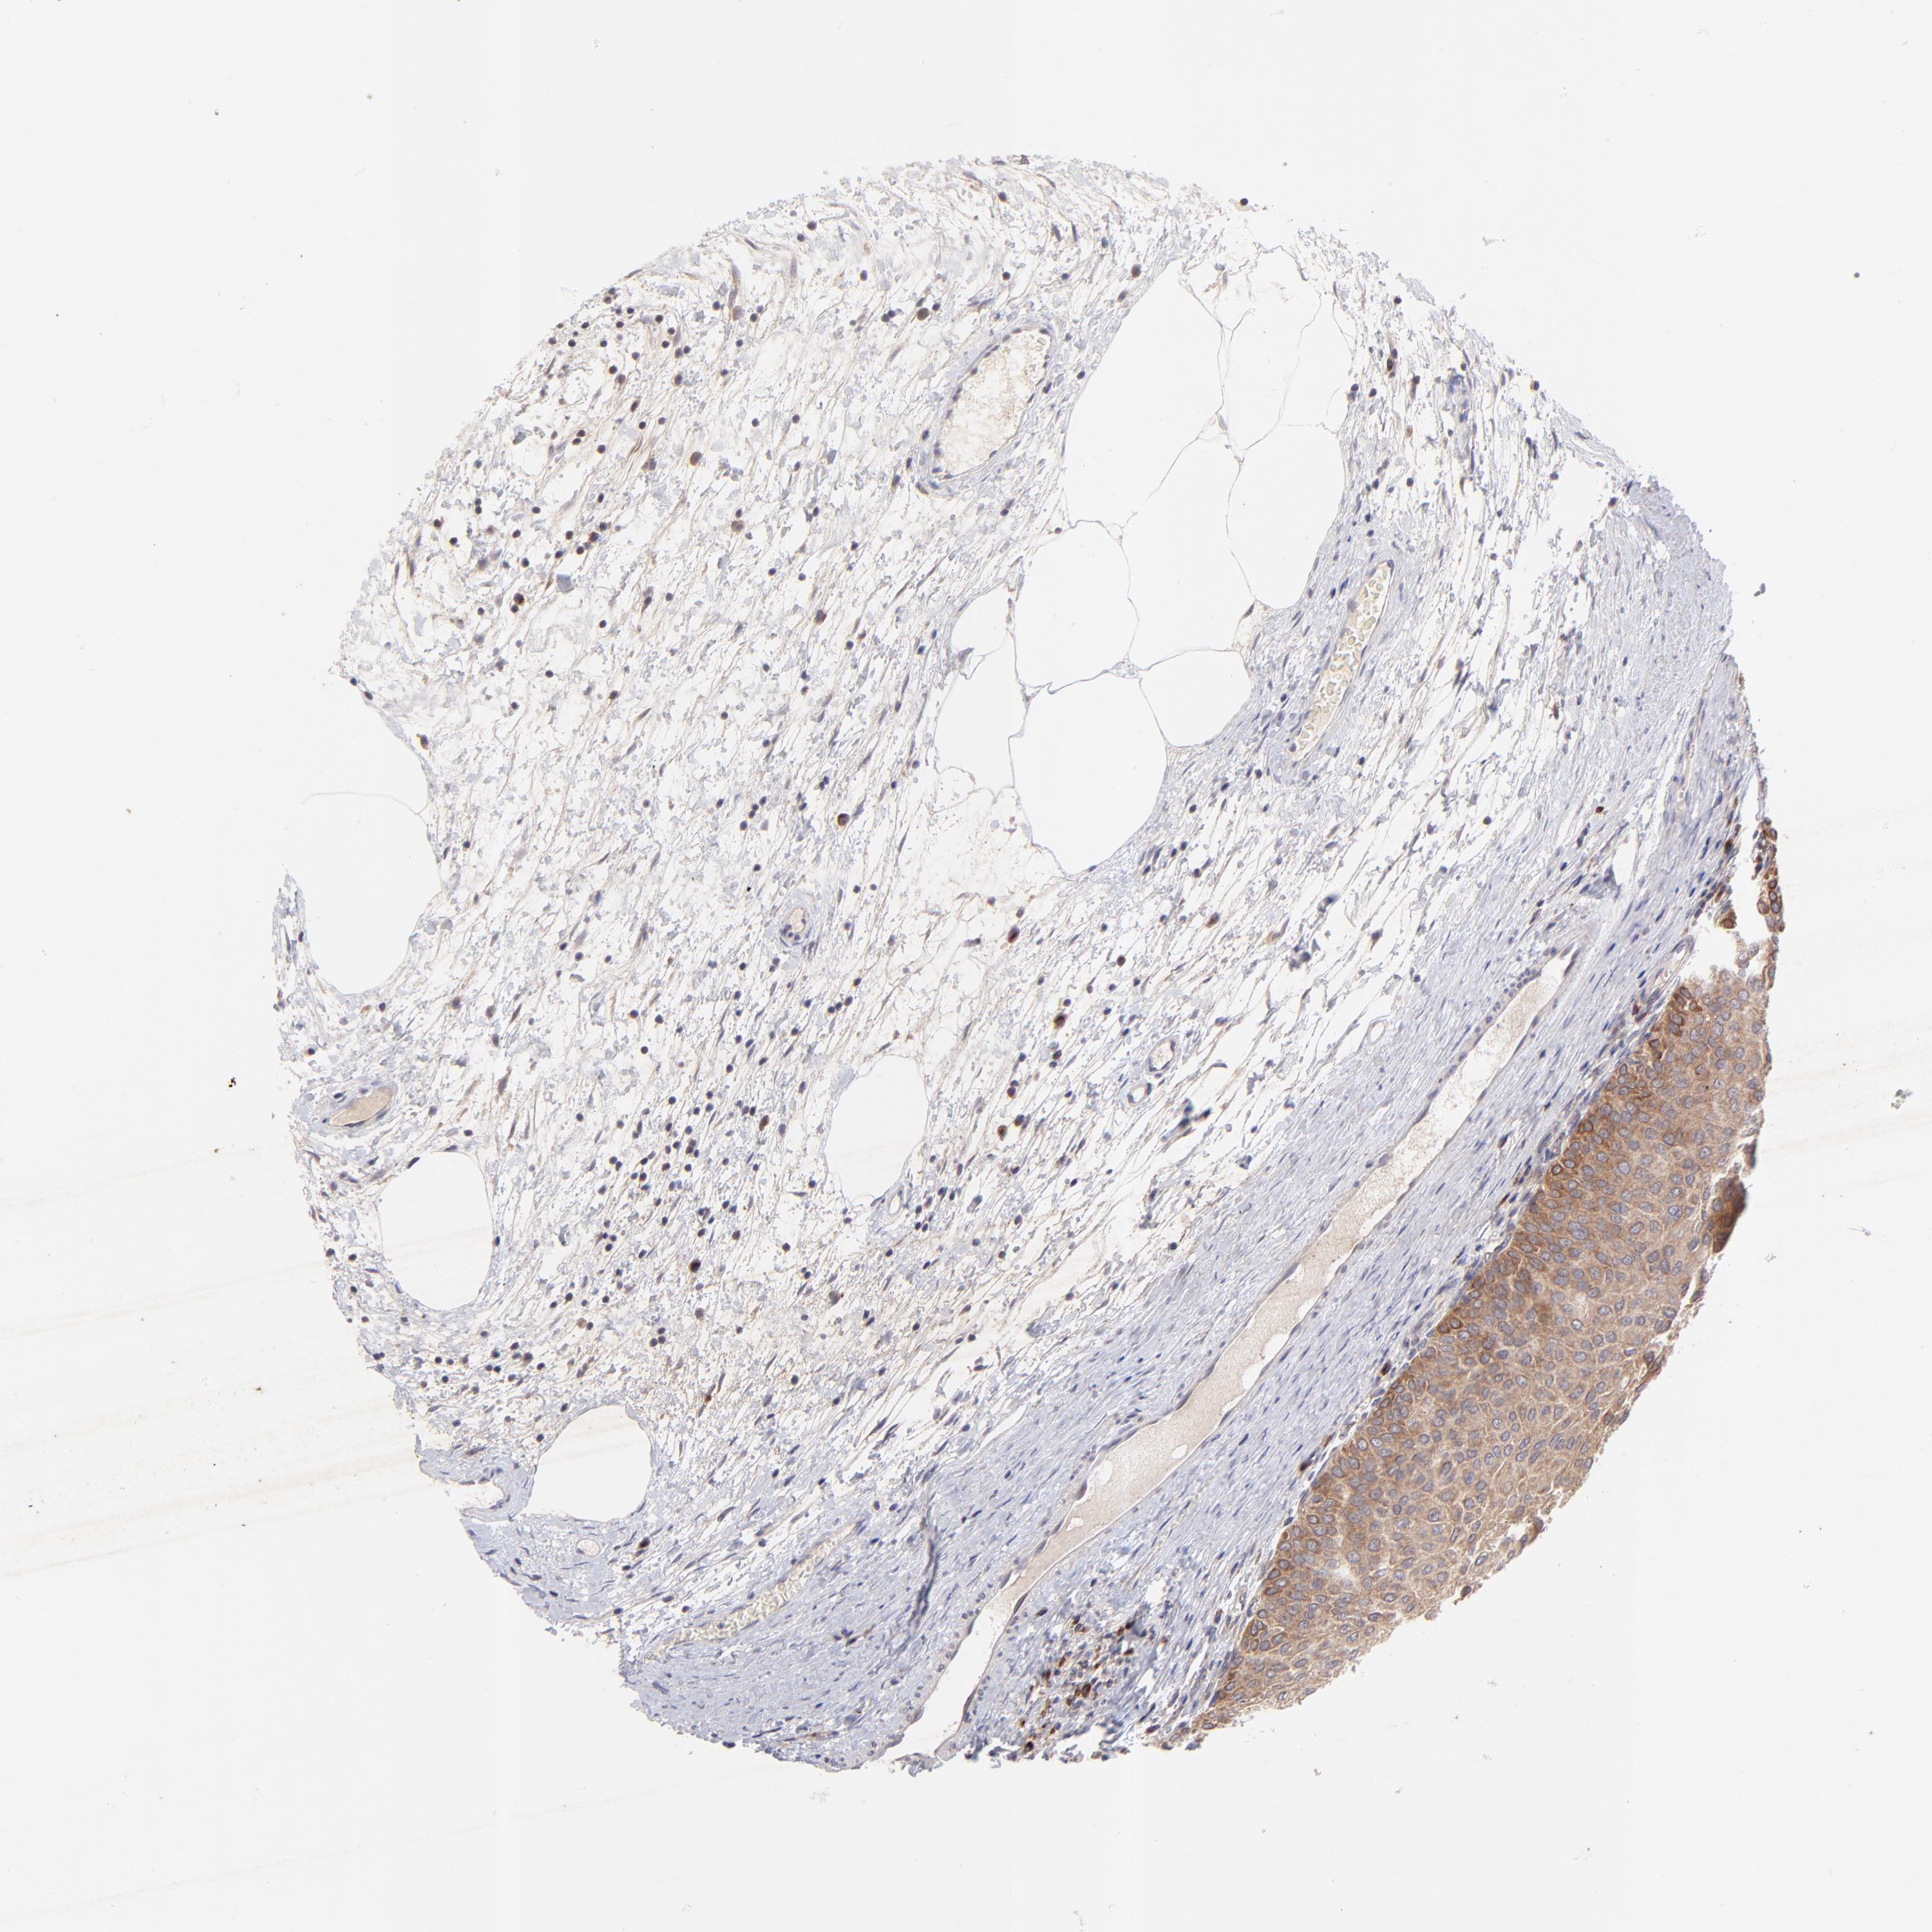

UROTHELIAL CANCER - Protein expressioni

A mouse-over function shows sample information and annotation data. Click on an image to view it in a full screen mode. Samples can be filtered based on level of antibody staining by selecting one or several of the following categories: high, medium, low and not detected. The assay and annotation is described here.

Note that samples used for immunohistochemistry by the Human Protein Atlas do not correspond to samples in the TCGA dataset.

Antibody stainingi

Antibody staining in the annotated cell types in the current human tissue is reported as not detected, low, medium, or high, based on conventional immunohistochemistry profiling in selected tissues. This score is based on the combination of the staining intensity and fraction of stained cells.

Each image is clickable and will lead to virtual microscopy that enables deeper exploration of all samples and also displays staining intensity scores, fraction scores and subcellular localization as well as patient and tissue information for each sample.

Antibody HPA003180

Staining

High

Medium

Low

Not detected

Intensity

Strong

Moderate

Weak

Negative

Quantity

>75%

75%-25%

<25%

None

Location

Nuclear

Cytoplasmic/membranous

Cytoplasmic/membranous,nuclear

Urothelial carcinoma, High grade

Urothelial carcinoma, Low grade